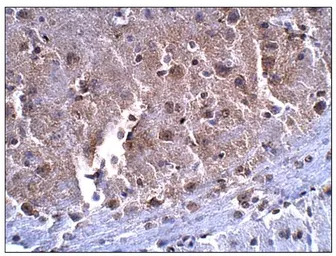

IHC-P analysis of mouse brain tissue using GTX47874 SLC7A10 antibody (N-terminal).

Dilution : 1:50